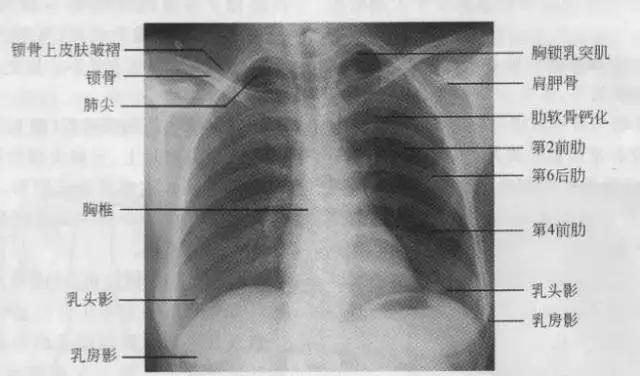

临床拍标准的胸部正位片其实是后前位片,如上图

正常胸部后前位片

7、胸廓

正常胸廓由软组织与骨骼组成,两侧对称。

① 骨性结构: 肋骨、锁骨、肩胛骨、胸椎

② 软组织结构:胸锁乳头肌、锁骨上皮肤皱褶、胸大肌、女性乳房 / 乳头